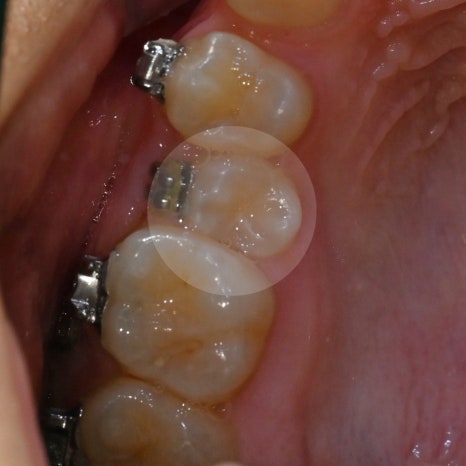

다행히 이번 케이스 에서는 위어금니 간 폭경과

아래 어금니 간 폭경의 비율은 정상이었습니다.

23.06.11

단, 과도한 수평피개 & 부족한 수직피개로

윗니가 아랫니를 충분히 덮지 못하는

개방교합(open bite)을 보이고 있던 상태입니다.

입천장 쪽으로 매복된 영구치의 일부가

관찰되었는데요.

부정교합을 맞추기 위해

2개의 상악 스크류 식립을 동반한

비발치 교정을 계획했으며,

교정 후 기존 안모 변화는 크지 않을 것으로 예상됩니다.